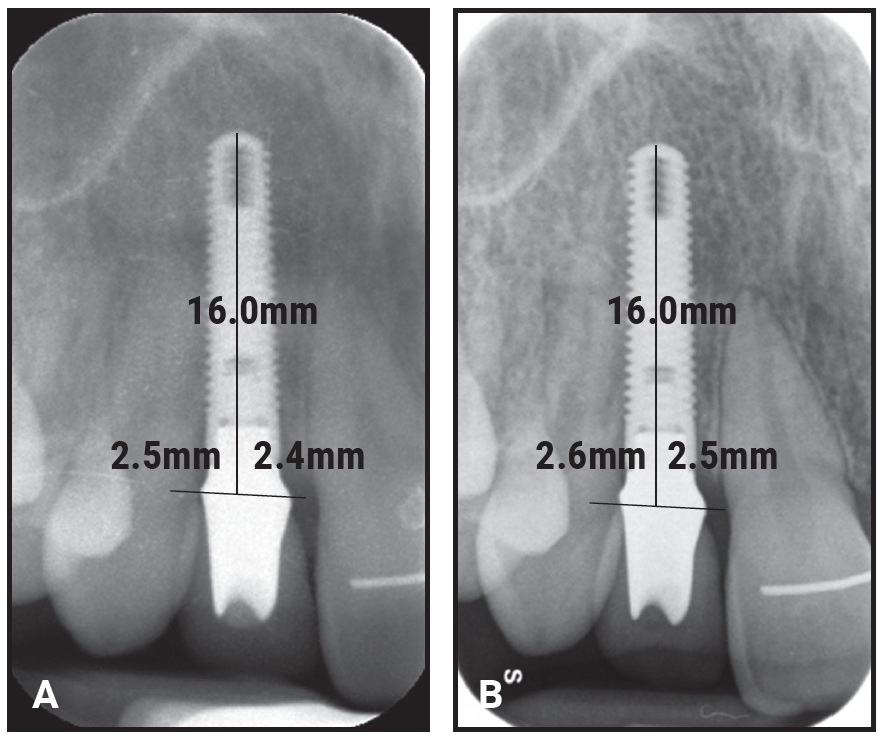

The one patient who developed a clinically relevant infraocclusion (1.5mm) showed a 2mm gingival recession and a 4mm probing depth at follow-up (Fig. 9). This patient had the only submerged implant—one that had been placed with a DBBM graft during orthodontic treatment. Without a provisional crown, the flap could not be sutured with vertical traction for better stabilization of the coagulum. Therefore, the DBBM granules were pushed apically, so that the implant was not completely covered. A cone-beam computed tomography scan confirmed the almost total absence of a facial bony wall over the implant. Superimposition of calibrated lateral and upper occlusal photographs taken at T1 and T2 indicated minor orthodontic relapse, with slight anterior bite opening and loss of upper incisor torque.

Fig. 9 Only patient to develop infraocclusion had submerged implant placed with graft (deproteinized bovine bone mineral particles) during orthodontic treatment. A. Minimal facial bony wall over implant. B. At final crown delivery. C. At follow-up, showing minor orthodontic relapse.